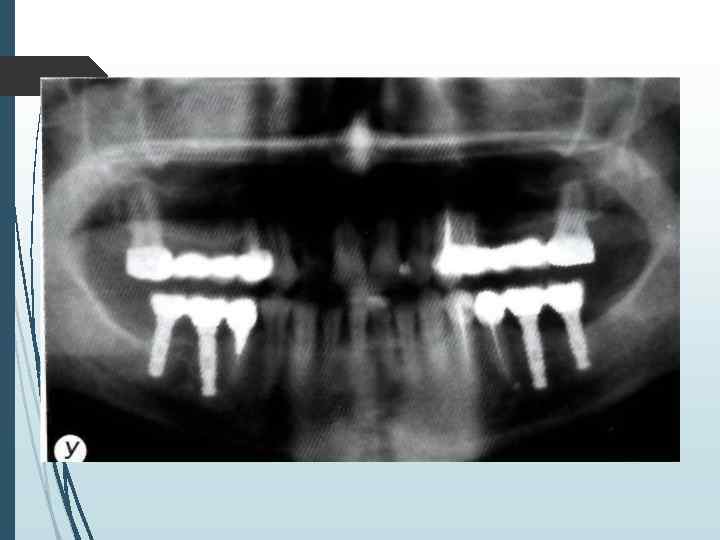

Однако следует учитывать, что даже при правильной укладке и методике ортопантомография даёт искажения реальных размеров челюстей до 10% по вертикали и до 20% по горизонтали. При неправильном положении пациента во время обследования или нарушении режима работы ортопантомографа искажения (увеличение размеров) могут достигать 32% по вертикали и 50 -70% по горизонтали

Компьютерная томография является одним из наиболее информативных методов рентгенологического обследования. С высокой степенью достоверности она позволяет определить высоту и ширину кости, топографию нижнечелюстных каналов и верхнечелюстных пазух, особенности архитектоники различных отделов челюстей, соотношение последних, а также создать трёхмерное изображение лицевого отдела черепа